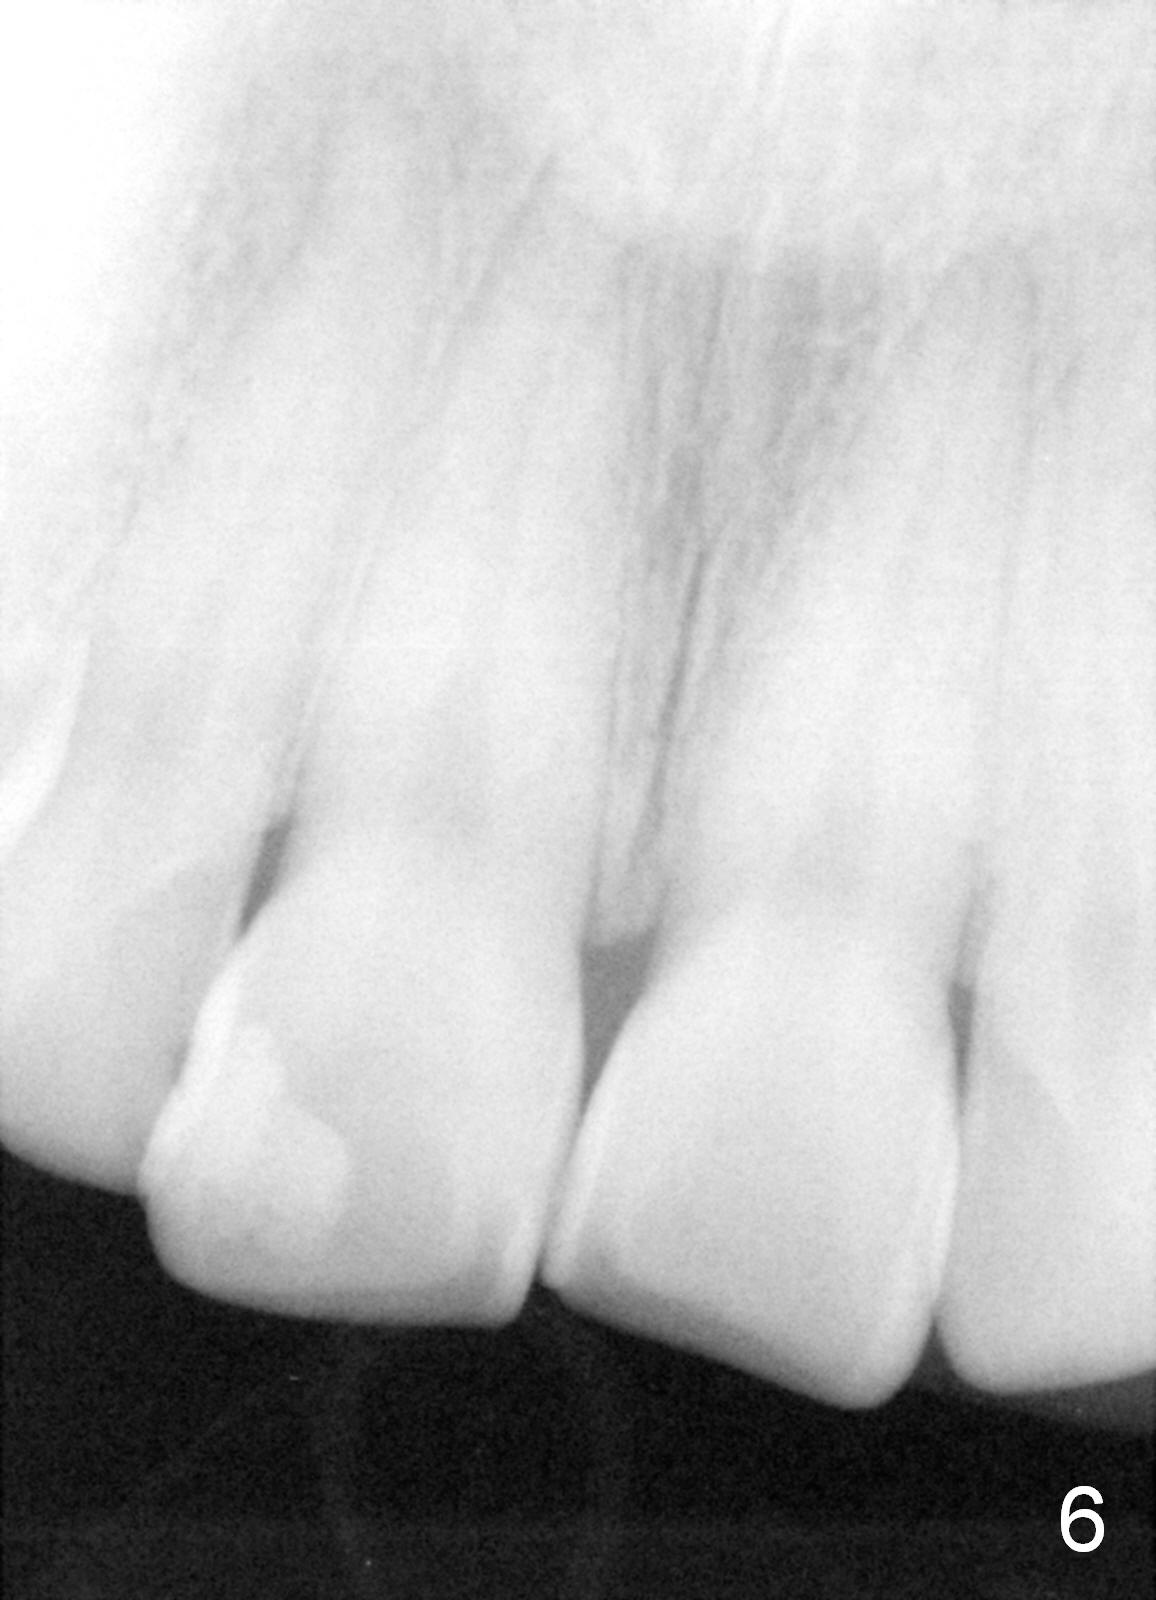

The panoramic X-ray (Fig.1) was taken on 12/12/2011 when the teeth #15 and 16 were extracted. The teeth #1 and 2 were removed half a year later. Bitewings (Fig.2-5), PAs (Fig.6,7) and upper occlusal mirror photo were taken on 02/11/2015. Pay attention to Fig.2.